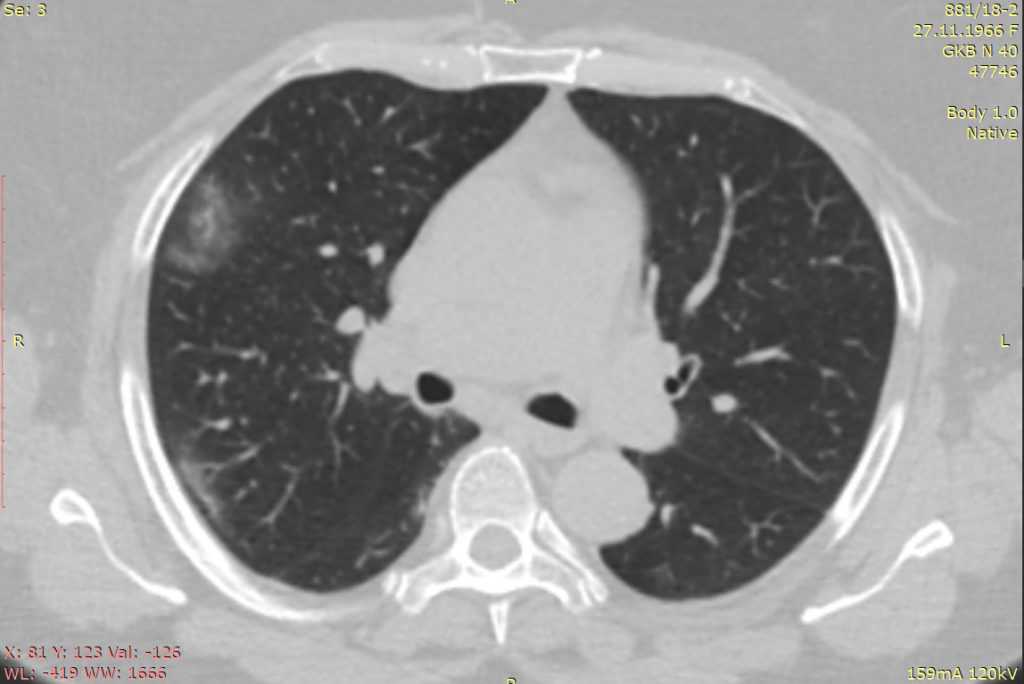

Клинический случай

У пациентки на фоне повышения температуры до 38,5 в течении 5 дней, слабости и потливости появился кашель со слизистой мокротой, потеря вкуса и боли в животе. На КТ ОГК в кортикальном слое легких, преимущественно, в их задне-базальных отделах определяются разнокалиберные участки уплотнения по типу «матового стекла» и консолидации, отдельные из них сращены с утолщенной костальной и задней средостенной плеврой. В плевральных полостях в наличии минимальное количество жидкости. Внутригрудной лимфоаденопатии не выявлено. Объем пораженной паренхимы легких не превышает 25%. Наличие участков консолидации коррелируют с выраженной клинической симптоматикой и присоединением кашля с мокротой.

Леднёв А.Г.